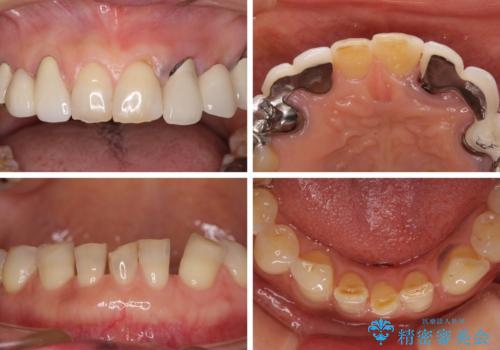

- 割れていると言われて放置してしまった歯や、前歯のデコボコなどが気になるとのことで来院された患者様です。

左上の歯は割れてしまっており、抜歯のうえインプラント治療が必要であり、他にも抜歯の必要な歯がある状態でした。

上顎はほぼ全ての歯をセラミッククラウンにて補綴治療を行う必要があるため、気になるデコボコや深い咬み合わせを改善するために下顎と上顎の臼歯部の矯正治療を行うこととしました。

並行して左下にはインプラントを埋入し、矯正治療を終えると同時に補綴治療を行うこととしました。

過蓋咬合(下顎前歯が隠れてしまうほどの深い咬み合わせ)のため、スムーズに歯が動かず矯正治療に時間がかかりましたが、無事に仕上げることができました。